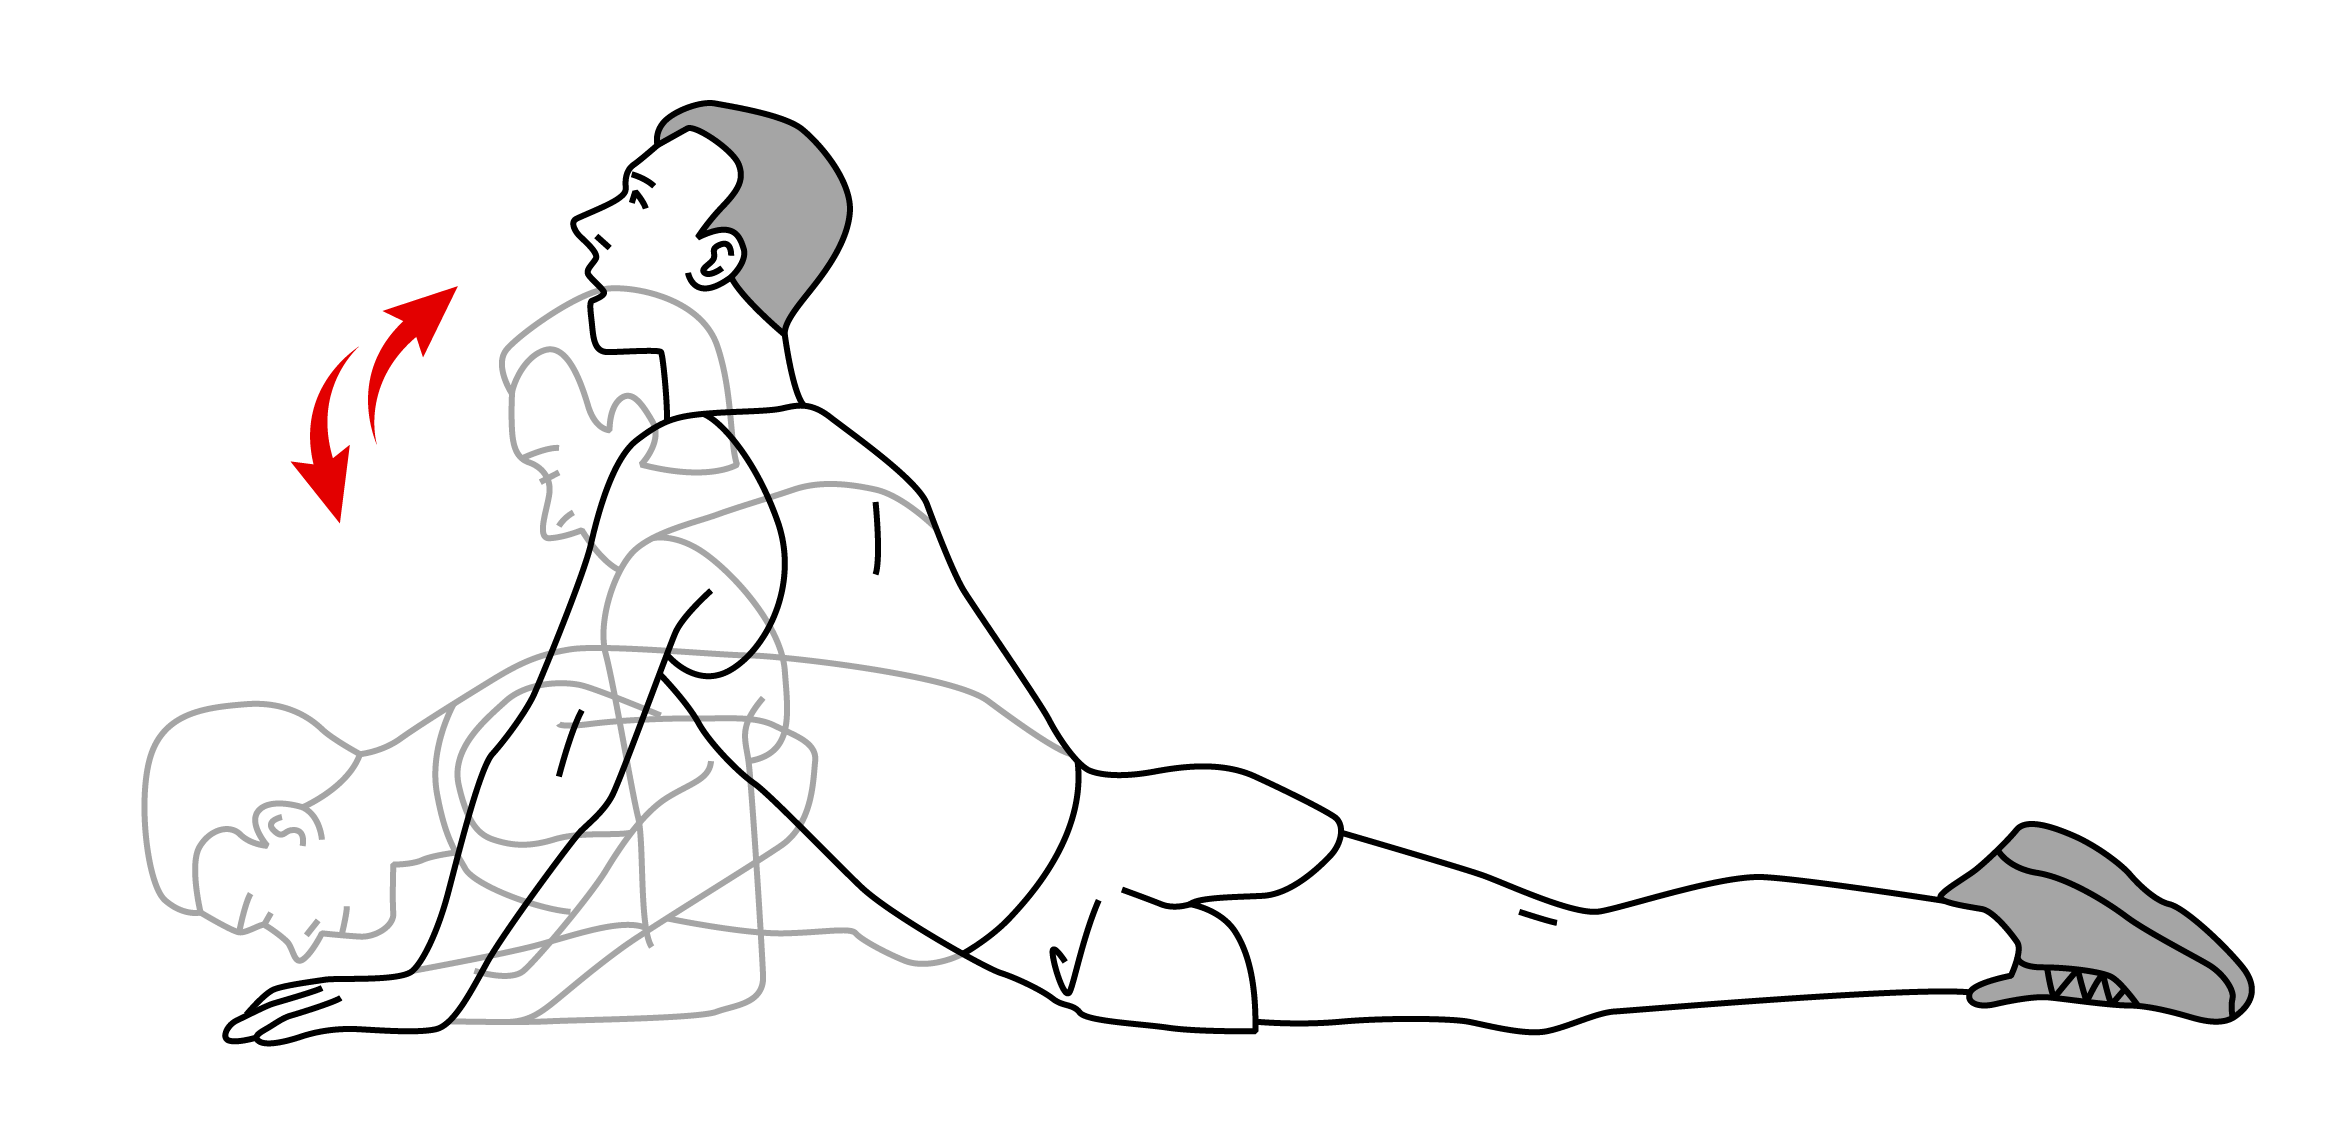

1) 맥켄지 운동

허리디스크의 통증은 대부분 후방 섬유륜을 찢고 뒤로 밀려 나오면서 신경을 압박하는 상황이 발생하여 허리를 굽힐 때 발생합니다. 이때 추천하는 운동은 맥켄지(Mckenzie) 운동입니다. 맥켄지 운동은 요추를 신전시킴으로 수핵을 앞으로 밀어 넣어 신경 압박을 완화시키는 운동 방법입니다. 재활 운동 시 중요한 것은 '통증'이며, 통증이 종아리에서 허벅지, 허벅지에서 골반으로 감소하는지 확인하면서 진행합니다. 만약 통증이 개선되지 않는다면, 다른 운동을 실시하여야 합니다.